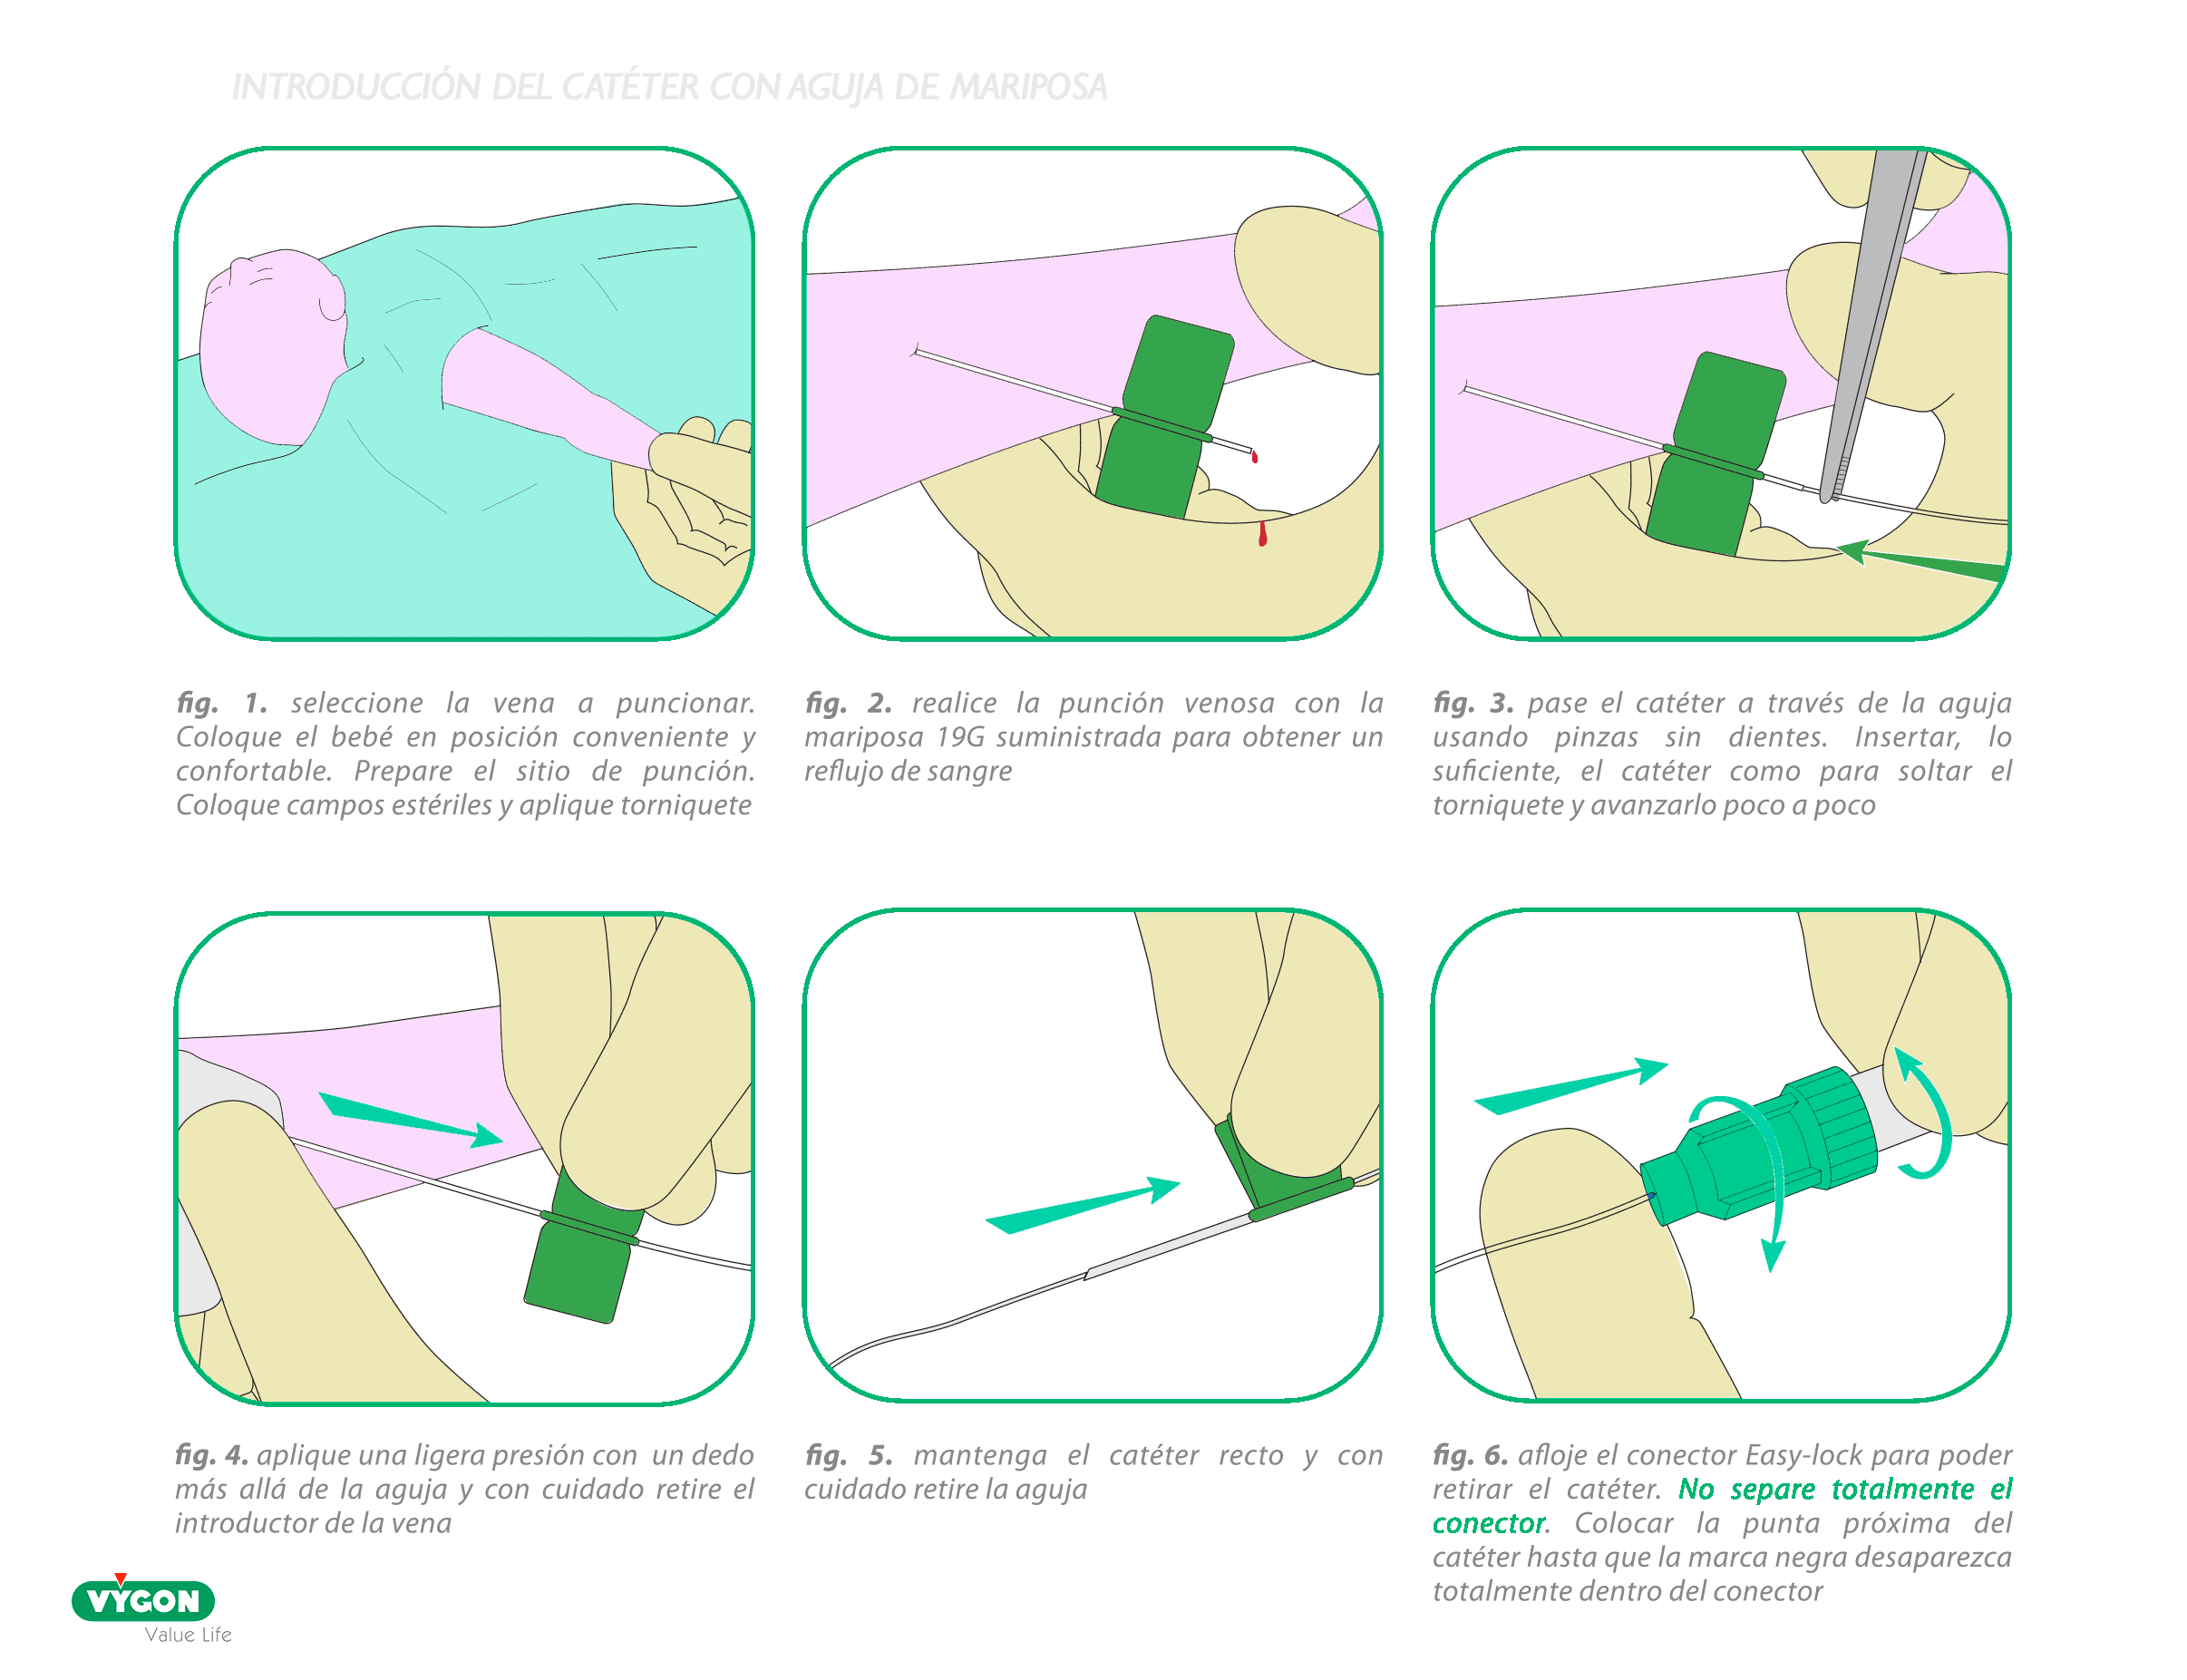

AGUJA MARIPOSA

La aguja mariposa es, desde hace años, uno de los dispositivos más conocidos por las enfermeras al ser un dispositivo muy presente en los servicios de UCIN en España. Este hecho, convierte a esta aguja en, probablemente, el introductor más controlado en lo que se refiere a técnicas de inserción.

Se usa únicamente con catéteres epicutaneos ya que es el único tipo de PICC neonatal que permite su retirada (catéter con conexión).

VENTAJAS

- Uso muy extendido

- Menor riesgo de coágulo debido al paso recto de la aguja (no tiene pabellón)

- Facilita la prensión dado que dispone de dos aletas flexibles.

INCONVENIENTES

- Impide el uso del catéter de una pieza: la presencia de la conexión en el catéter de 2 piezas aumenta el riesgo de infección

- Dispone de una aguja más larga que otros introductores (27 mm) con un diámetro de 19G: estas dos características lo convierten en un introductor demasiado grueso para las venas de los grandes prematuros

- La detección del reflujo de sangre no es inmediata: aguja opaca

- La inserción del catéter en el introductor resulta delicada al ser de un diámetro muy similar (la extremidad proximal de la aguja no está ensanchada)